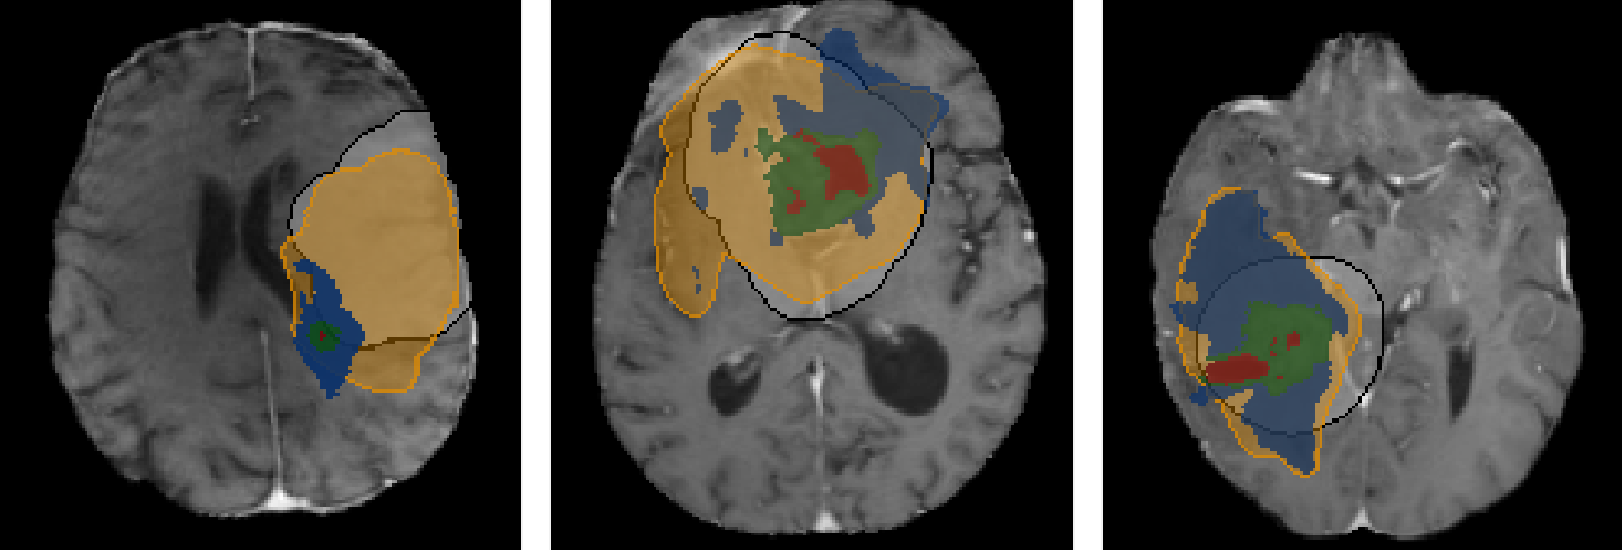

Accurate modeling of brain tumor growth holds great promise for improving radiotherapy planning by capturing microscopic infiltration that remains invisible on standard imaging. In this talk, I will present a series of advances toward patient-specific biophysical and data-driven models of glioma growth. Our work integrates mechanistic tumor modeling with machine learning to enable accurate, efficient, and individualized predictions of tumor spread. By combining reaction-diffusion formulations with structural information from diffusion tensor imaging, we capture how white matter architecture shapes glioma invasion. A learnable inference framework then bridges these biophysical models with data-driven parameter estimation, enabling fast and robust reconstruction of patient-specific tumor cell distributions from MRI. Together, these developments move toward clinically applicable tumor growth modeling for personalized radiotherapy planning.